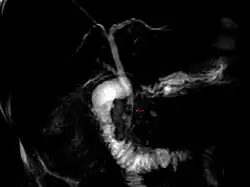

MRCP-Aufnahme der Gallenwege mit Gallensteinen (Pfeil, dunkle runde Aussparungen durch Steine)

• Ultraschalluntersuchung (Sonografie): Gallensteine und auch Entzündungen der Gallenblase lassen sich sonografisch gut darstellen. Kleine Cholesterinsteine, die den Gallengang verstopfen können, werden jedoch mitunter nicht gefunden.

• MRCP (magnet-resonanztomographische Cholangiopankreatikographie)